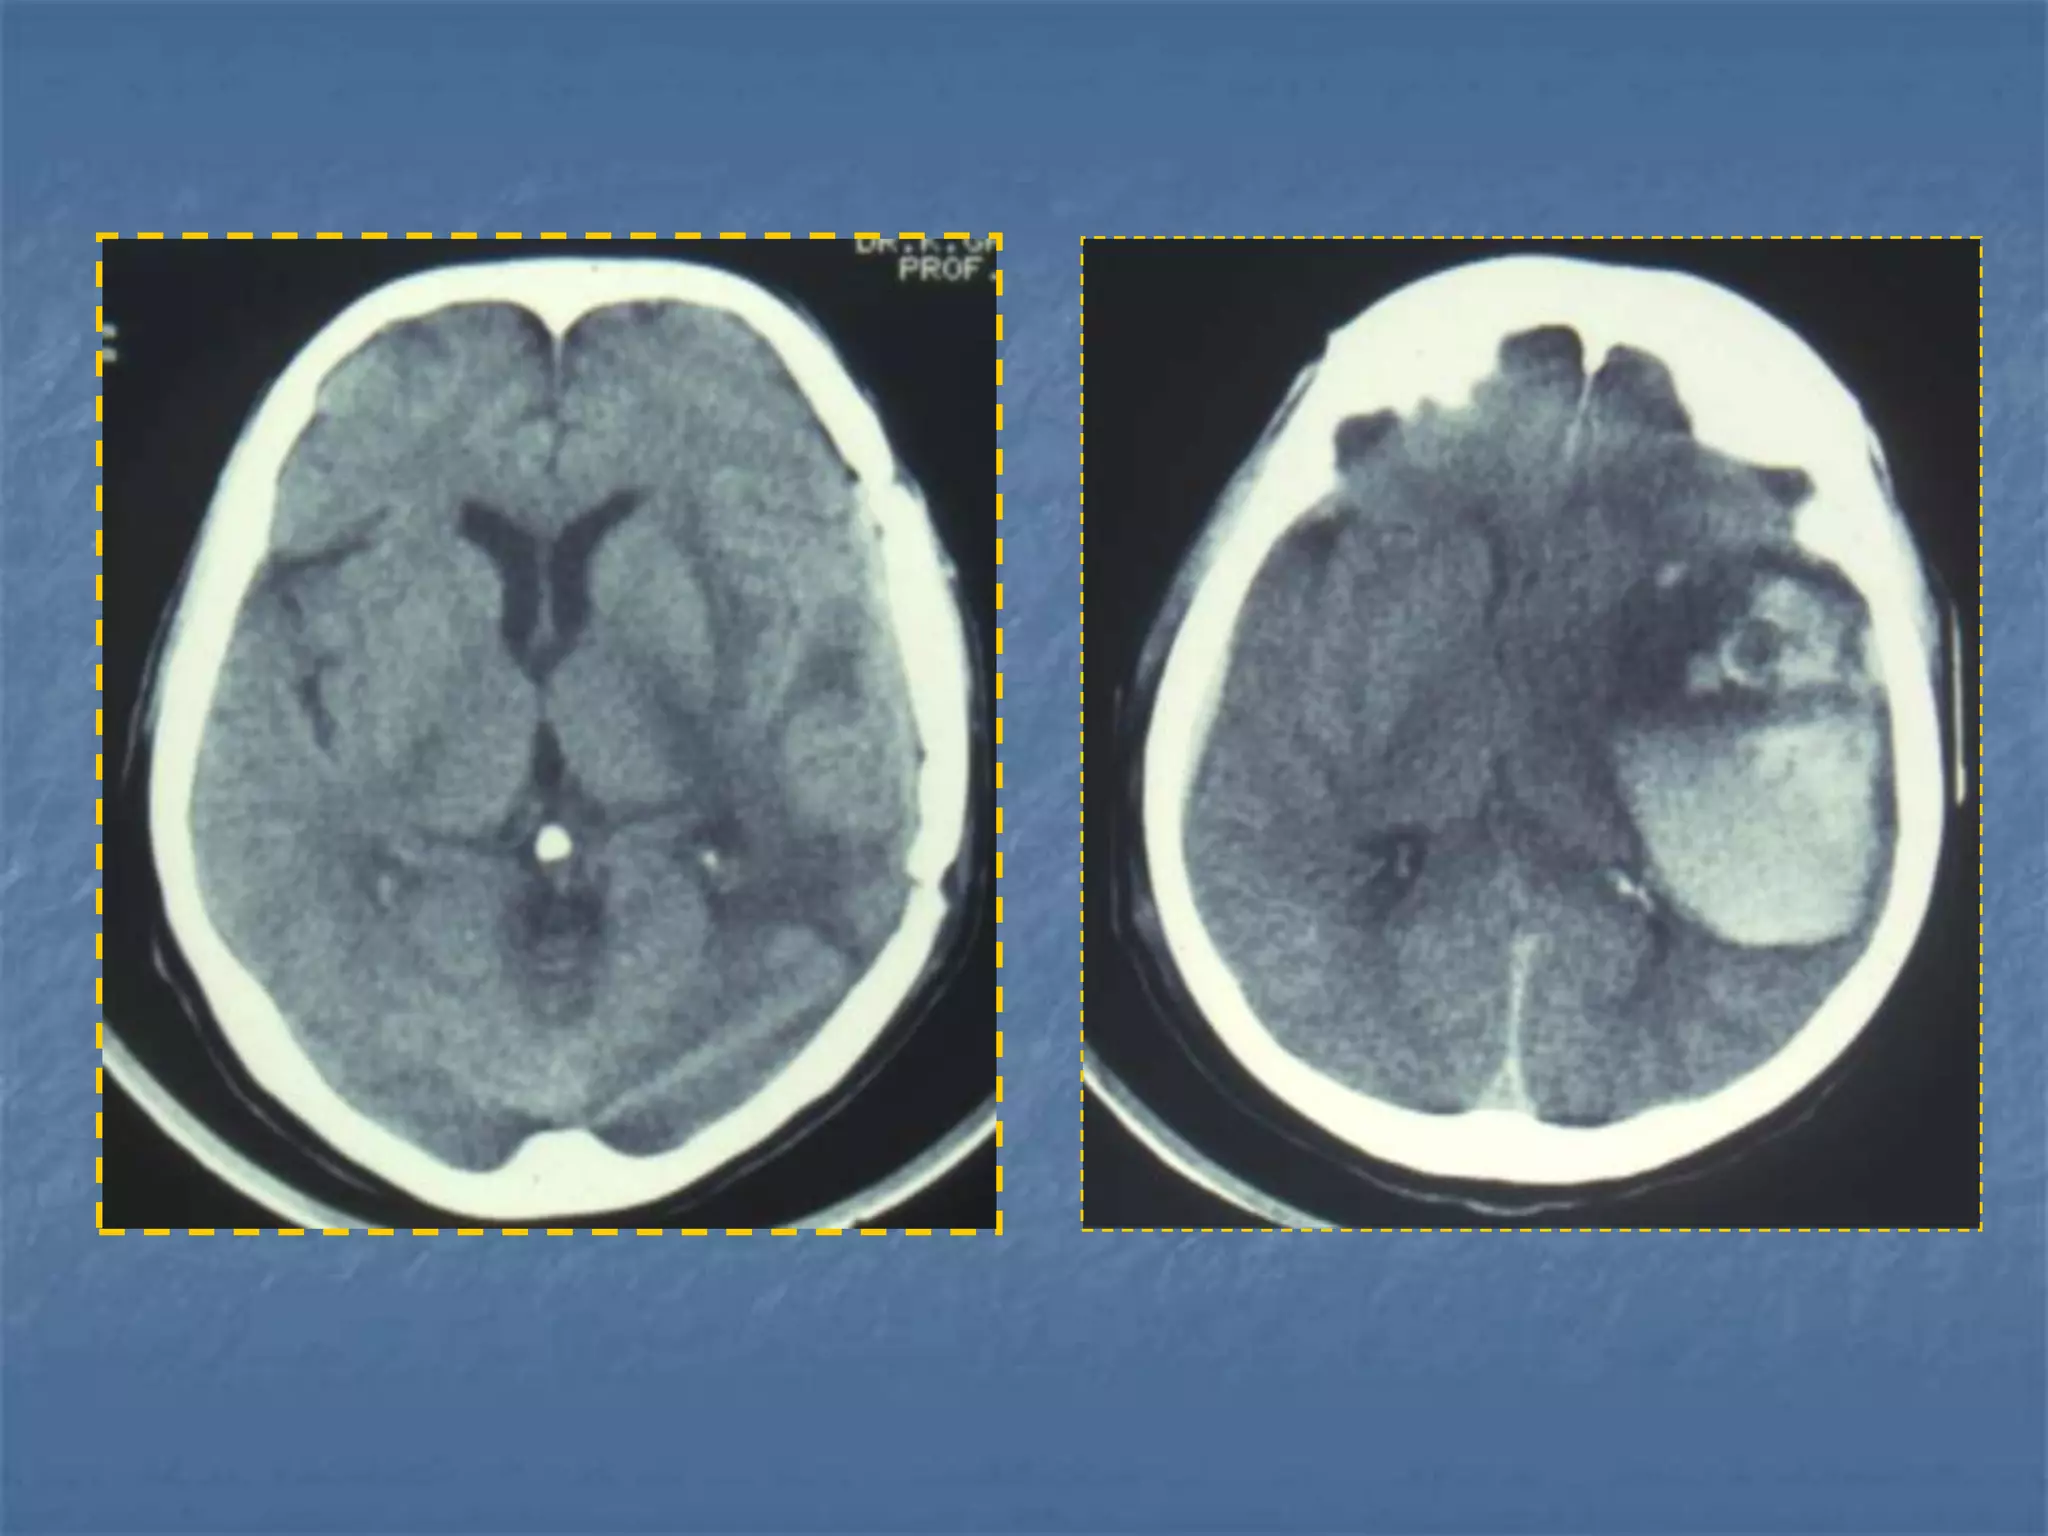

Subarachnoid hemorrhage

 CT is currently the imaging modality of choice because

of its high sensitivity for the detection of subarachnoid

hemorrhage. CT is most sensitive for acute

subarachnoid hemorrhage. After a period of days to

weeks CT becomes much less sensitive as blood is

resorbed from the CSF. If there is a strong clinical

indication, LP may be warranted despite a negative CT

since small bleeds can be unapparent on imaging.

On CT, a subarachnoid hemorrhage appears as high

density within sulci and cisterns. The insular regions

and basilar cisterns should be carefully scrutinized for

subtle signs of subarachnoid hemorrhage.

Subarachnoid hemorrhage may have associated

intraventricular hemorrhage and hydrocephalus.



 In the absence of trauma, the most common cause

of subarachnoid hemorrhage is a ruptured cerebral

aneurysm. Cerebral aneurysms tend to occur at

branch points of intracranial vessels and thus are

frequently located around the Circle of Willis.

Common aneurysm locations include the anterior

and posterior communicating arteries, the middle

cerebral artery bifurcation and the tip of the basilar

artery. Subarachnoid hemorrhage typically presents

as the "worst headache of life" for the patient.

Detection of a subarachnoid hemorrhage is crucial

because the rehemorrhage rate of ruptured

aneurysms is high and rehemorrhage is often fatal.